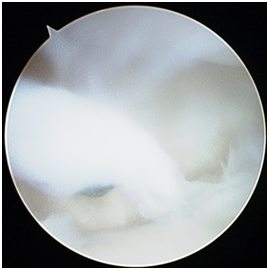

Radio-carpal arthroscopy was done with the 3-4 (between the 3rd and 4th dorsal extensor compartments) portal as the viewing portal and the 4-5 (between the 4th and 5th dorsal extensor compartment) portal as the working portal. The joint was very difficult to scope due to the findings of a “snowstorm” of fibrotic plica bands (Figure 1), thickened synovium covering the TFCC (Figure 2) and further synovitis in the ulno-carpal recess (Figure 3). After debriding all these layers of tissues, the TFCC was found to be intact but stretched over the congenitally deformed ulnar head (Figure 4). There was also early stage chondromalacia of the lunate fossa of the radius.

Figure 3 Radio-carpal arthroscopy left wrist (triquetrum on top, TFCC at bottom) after the plica bands and the thickened synovia has been removed, demonstrating further synovitis in the ulnocarpal recess.